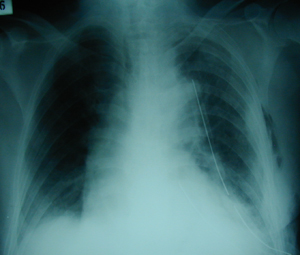

Εικόνα 4

Οπισθιοπροσθία ακτινογραφία του θώρακος μετά από τη διενέργεια ερευνητικής περιορισμένης θωρακοτομής. Πλήρης εκκένωση του υγρού (αίματος) και πλήρης έκπτυξη του πνεύμονος και επαναφορά του μεσοθωρακίου σε φυσιολογική θέση.